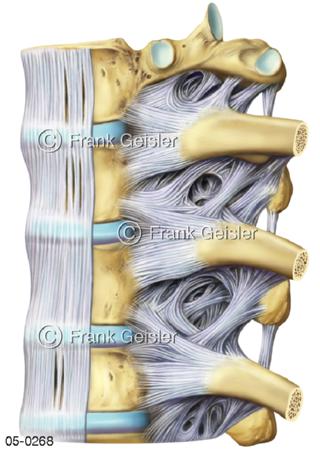

Bildergalerie Skelettsystem

Bilder zum Skelettsystem zeigen die Stützstruktur des menschlichen Körpers, die Knochen, eine besonders harte Form des Bindegewebes und Stützgewebes, welche das menschliche Skelett bildet, die Knochen des Stammes, der Extremitäten sowie der Gelenke